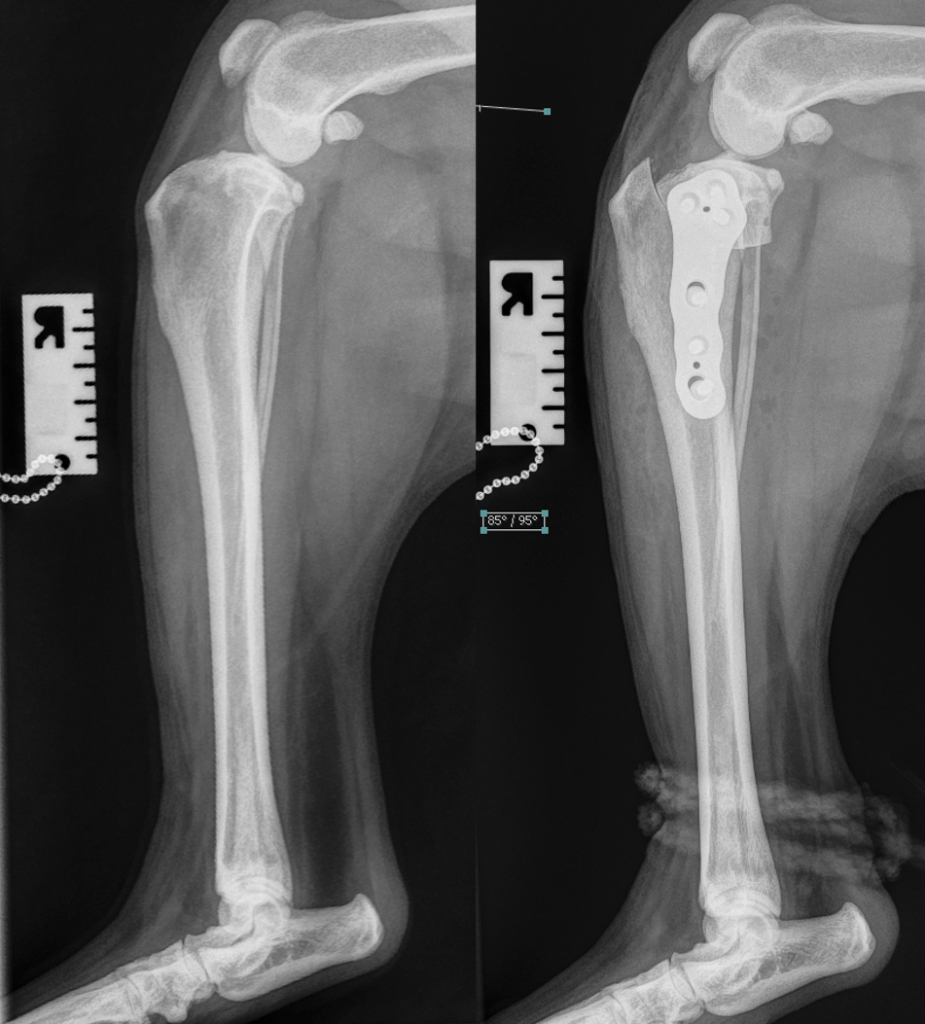

Based on the best evidence that is currently available, it is very likely that the most effective surgical treatment for CCL failure is the tibial plateau levelling osteotomy (TPLO). In this procedure, the backward slope at the top of the tibia is “levelled” so that the natural tendency for the femur to slide down that slope is neutralised. More surgeons recommend this technique than any other, and there is good quality evidence that it is more effective than some other popular surgical options. You can watch a video that explains how TPLO is performed and helps to stabilise the stifle joint HERE.

X-ray images (radiographs) can be useful in the diagnosis of CCL failure. An increased volume of joint fluid (called an effusion) can be seen on radiographs, and, if the problem has been present for a few weeks or more, there might be signs of osteoarthritis. Radiographs are also useful in ruling out other causes of stifle joint pain and lameness.